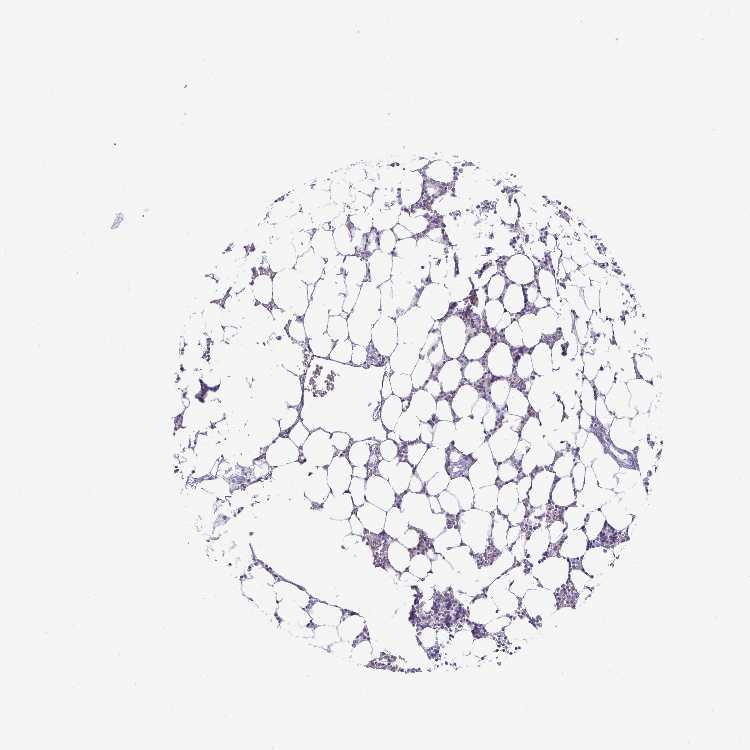

BONE MARROW - Antibody stainingi

Antibody staining in the annotated cell types in the current human tissue is reported as not detected, low, medium, or high, based on conventional immunohistochemistry profiling in selected tissues. This score is based on the combination of the staining intensity and fraction of stained cells.

Each image is clickable and will lead to virtual microscopy that enables deeper exploration of all samples and also displays staining intensity scores, fraction scores and subcellular localization as well as patient and tissue information for each sample.

Antibody HPA054437Antibody HPA058511Antibody CAB015122

Hematopoietic cells Not detectedNot detectedHigh

BONE MARROW - HPA RNA-seqi

The RNA-seq details section shows detailed information about the individual samples used for the transcript profiling and results of the RNA-seq analysis.

Information about each individual sample is listed below, including gender, age, a tissue section image and estimated fractions of cell types. nTPM (normalized transcripts per million) values give a quantification of the gene abundance which is comparable between different genes and samples.